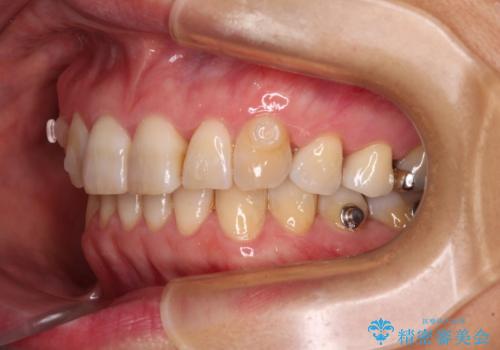

インビザラインは、ワイヤー矯正と異なり、患者様がしっかりと使うということが治療成功の絶対必須条件となります。

十分な装着時間が達成できず、治療途中で後戻りを起こすことがあり、インビザラインの有効期限内に終了させることができませんでした。

ワイヤー矯正や別システムのマウスピース矯正を利用することで、何とか終了させることができました。